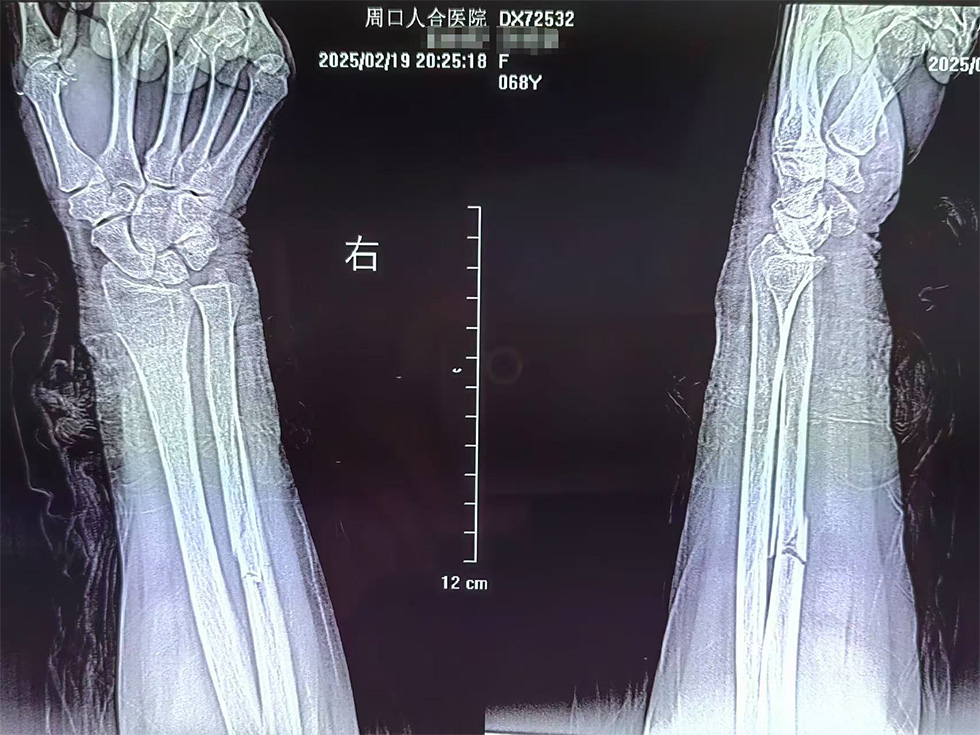

患者许大娘,67岁,因意外车祸导致尺骨粉碎性骨折。传统的切开复位内固定手术创伤大、出血多,术后恢复时间长,且容易对骨折端血运造成破坏,影响骨折愈合。

术 前